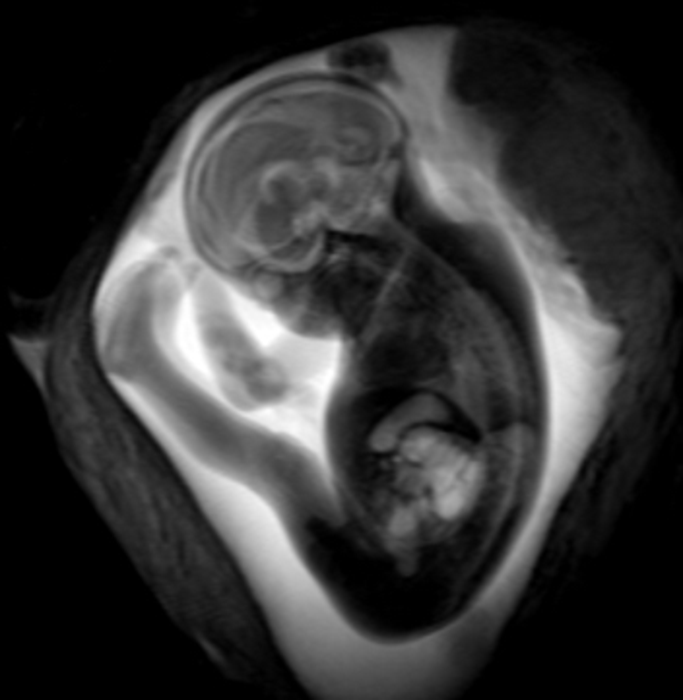

Dr. Stöcklein and colleagues used fetal MRI to study 33 patients with COVID-19 infection during pregnancy. The patients were roughly 28 weeks into their pregnancies, on average, with symptom onset occurring at a mean of just over 18 weeks into the pregnancy. The most common maternal symptoms were loss or a reduced sense of smell and taste, dry cough, fever and shortness of breath.

Two board-certified radiologists with several years of experience in fetal MRI evaluated the scans. They found that the brain development in the assessed areas was age-appropriate in all fetuses. There were no findings indicative of infection of the fetal brain.

“In our study, there was no evidence that a maternal SARS-CoV-2 infection has any effect on the brain development of the unborn child,” Dr. Stöcklein said. “This fact should help to reassure affected parents.”